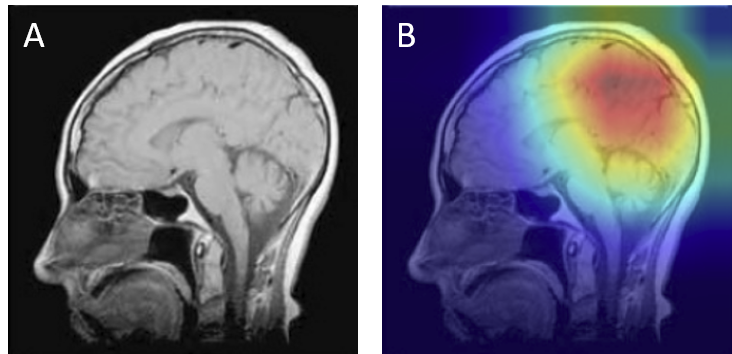

Grad-CAM visualizations of correctly classified cases confirm that the model focuses on regions consistent with radiological expectations. In these overlays, warmer colors (red and orange) highlight the areas where the network places the greatest emphasis during prediction, while cooler colors (blue) correspond to regions with minimal contribution. This distinction allows direct inspection of whether the model bases its decision on clinically relevant cues.

For gliomas, the heatmaps align with intra-axial lesions exhibiting infiltrative margins (Figure 8). Meningiomas are accurately identified at dural or peripheral attachment sites, consistent with their extra-axial presentation (Figure 9). Pituitary adenomas are localized to the sella turcica with concentrated red activation at the lesion boundaries (Figure 10). Finally, in no tumor cases, the activation maps remain diffuse or midline-focused without strong hotspots, consistent with normal anatomy (Figure 11). The correspondence between the model's attention and radiological landmarks indicates that the network is learning meaningful diagnostic features rather than relying on spurious correlations.

Figure 10: Pituitary Adenoma — original (A) vs. Grad-CAM (B), correct model prediction.

Pituitary Correct